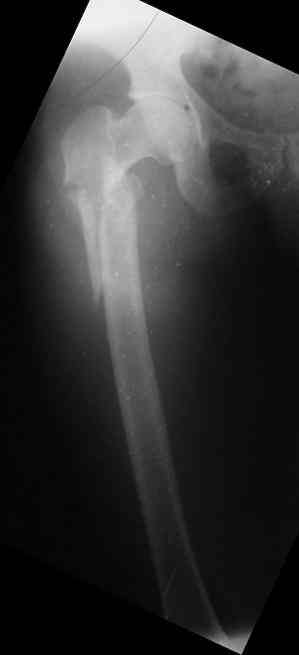

Male, 75 yrs old.

Right hip fracture as an interthrocanteric with extension to diaphysis Tronzo V.